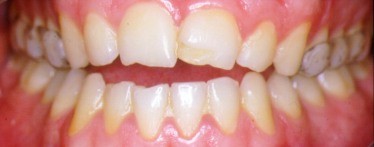

FIGURA 5.- Férula en boca. Vista

frontal.

mordida abierta anterior que impide el mordisqueo.

Para

apreciar las zonas de desgaste y abrasión en

incisivos.